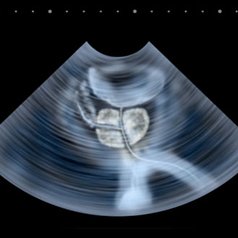

Prostat bezi erkeklerde bulunan idrar kesesinin(mesane)...

devamı için tıklayınız.Klinik BPH tanısı için hastanın şikayetleri, klinik muayene ve birtakım tetkikler birlikte...